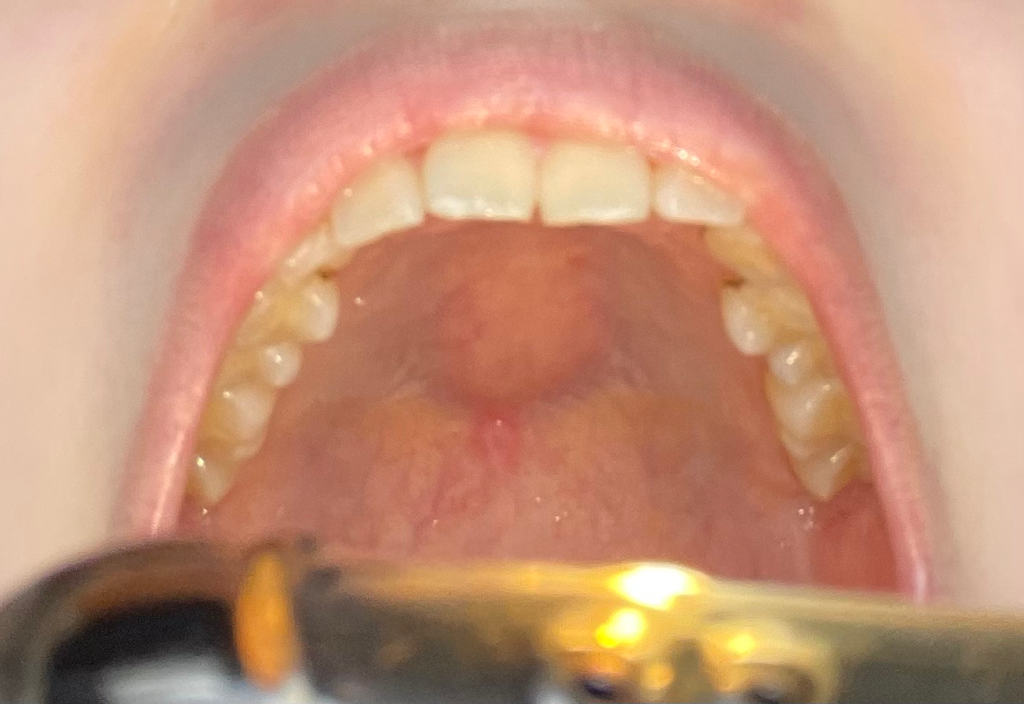

입천장 통증과 혹 구강암 일까요?

몇년동안 가끔 혀를 굴리다보면 느껴졌었는데 원래 있는건줄 알았어요.. 거울로 확인해보니 하얗게 정중앙에 있네요 누르면 아프고 평평하지 않고 볼록 튀어나와있어요 장기간동안 안없어지고 이상태이면 암일까요?

• 1번 째 사진